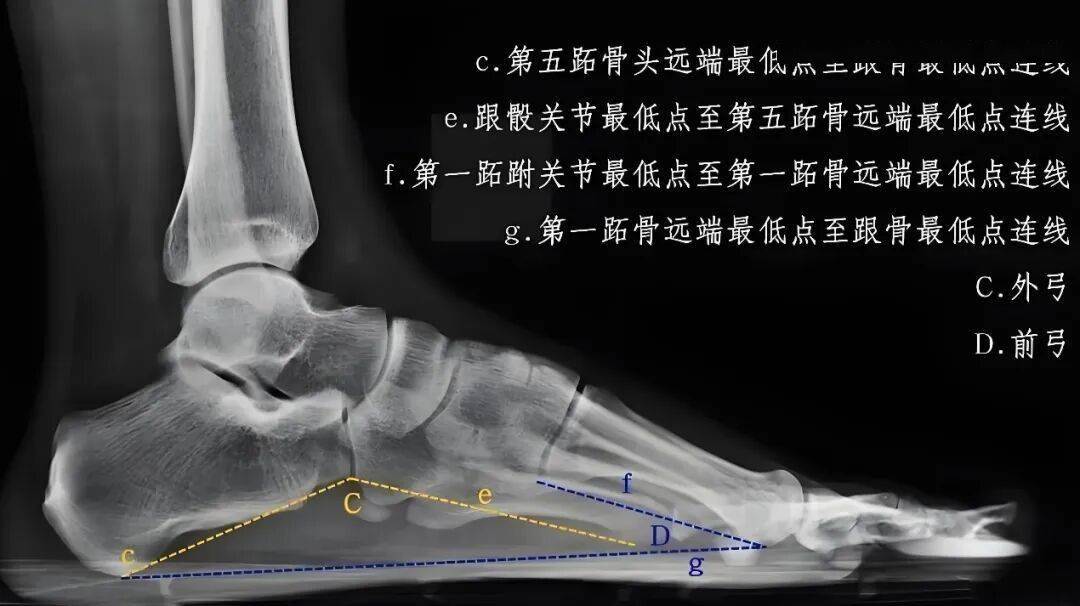

临床上诊断平足的“金标准”是拍摄 负重位X片,如上图所示,通过测量特定位置角度,就能客观判断足弓塌陷程度。